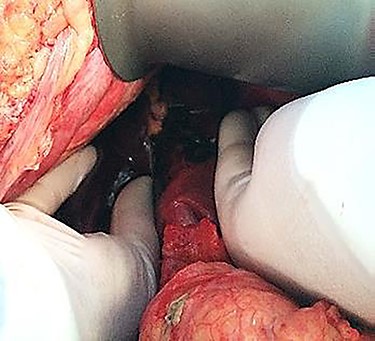

An emergency c-section was performed, during which a massive hemoperitoneum was observed. It was subsequently converted to median laparotomy and a subcapsular hepatic hematoma involving the entire left lobe was found, with rupture and active hemorrhage. Hepatic packing was performed. However, the patient continued to bleed profusely. Therefore, a Vicryl® prosthesis involving the left lobe was placed to effectively control the hemorrhage (Fig. 1).

As far as the surgical approach is concerned, an immediate hepatic packing was performed in both patients. However, it was not possible to fully control the hemorrhage in the first patient, so a Vicryl® prosthesis was placed, commonly used in post-traumatic splenic lacerations. It was adapted ‘in situ’ to this particular situation to cover the entire left lobe of the liver. This is an uncommon approach according to the literature. It is mainly described in the context of trauma surgery as a life-saving measure.